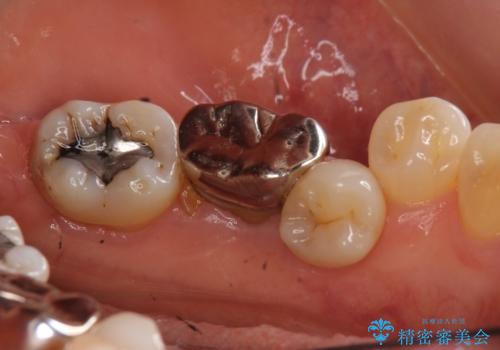

奥歯の部分矯正を行うことで、歯の傾きが良くなり、結果神経を取らずにブリッジを入れていくことができました。

通常矯正治療後は歯並びが戻らないように保定が必要ですが、ブリッジを入れているので歯並びは戻らないため保定が不要です。

部分矯正と補綴の相性は良いといえます。